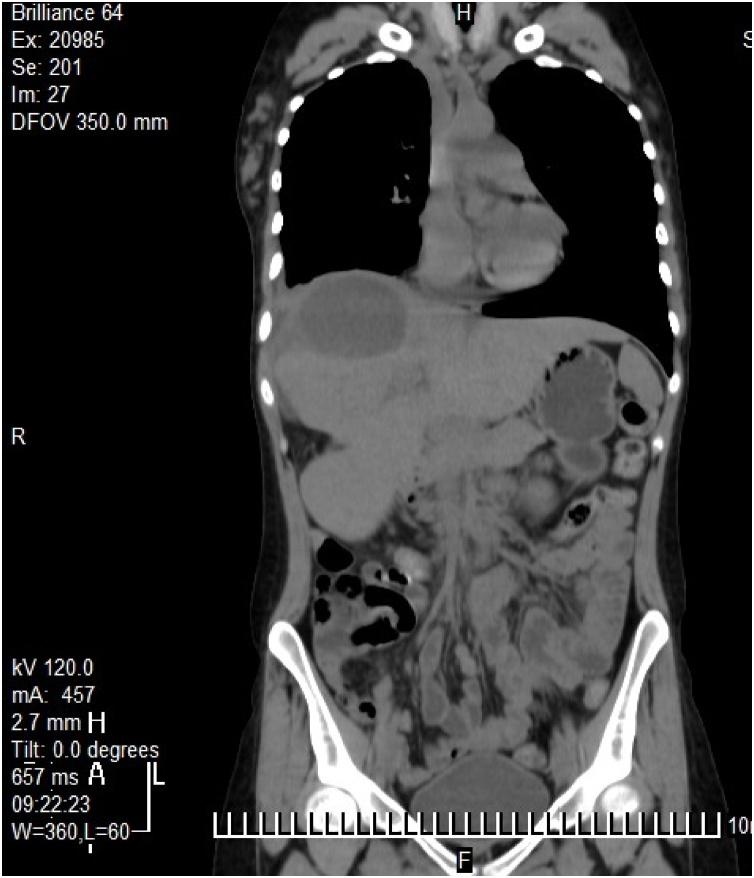

PRESENTATION OF CASE

We report on a 45-year woman suffering from alveolar echinococcosis with a huge cystic mass and difficulty of differential diagnosis. She was hospitalized for surgery with primary diagnosis of hydatid disease. The liver carcinoma was suspected during surgery due to the huge size and structure of the mass. This mass was totally removed. The alveolar echinococcosis was confirmed by histopathological examination.

病例介绍

我们报告了一名45岁患有肺泡型棘球蚴病的女性,其患有巨大囊肿性肿块且鉴别诊断困难。她因初步诊断为包虫病而住院接受手术。由于肿块的巨大尺寸和结构,手术期间怀疑为肝癌。该肿块被完全切除。经组织病理学检查确诊为肺泡型棘球蚴病。